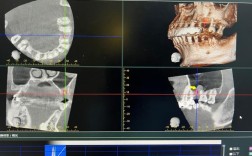

- 拍摄口腔X光片(根尖片),通常还需要锥形束CT(CBCT),这是评估骨量、骨密度、神经血管位置、判断愈合情况和制定种植计划的金标准。